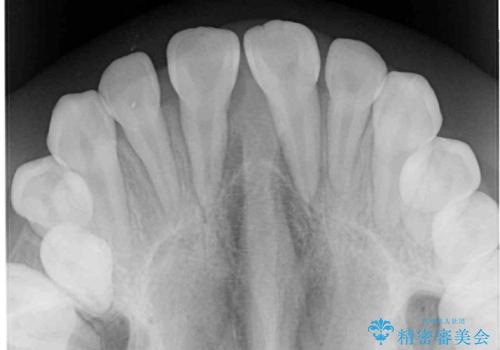

上下の骨幅を改善したことで、スムーズに歯列矯正を行うことができました。

インビザライン治療開始直後に遠方に引っ越しをされたため、通院間隔が長くなり、治療期間が長くなりましたが、しっかりと治療を行うことができました。